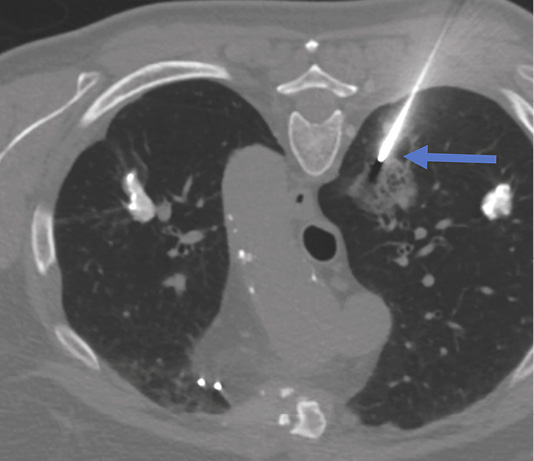

Lung biopsy procedure was performed under local anesthesia in a prone position and the patient was instructed of shallow breathing. 17 gauge coaxial needle was inserted under CT guidance and proceeded up to the lung needle while lung biopsy was performed with 18 gauge needle with automated biopsy gun (Figure 2) sampling two biopsy specimen cores.

Shortly after second biopsy patient became disorientated, started moving on the CT table. Patient’s language and behavior was also changed, and communication was difficult.

Immediate head CT was performed suspecting neurological pathology. Small air foci were found in peripheral area of left parietal lobe – a clear sign of air embolism (Figure 3). Patient was treated with 100% oxygen.